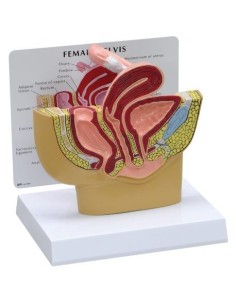

Dal cranio in 22 parti con incastri magnetici ai modelli di colonna vertebrale, da quelli di articolazioni a quelli di cuore, ogni pezzo della nostra collezione è progettato per un’immersione totale nello studio dell’anatomia umana. I nostri modelli, realizzati tramite scansioni di ossa vere, garantiscono un’esperienza tattile autentica e una fedeltà di peso quasi identica agli originali.

Essenziali per studenti e professionisti, i nostri modelli anatomici sono strumenti didattici che permettono di osservare le strutture anatomiche con precisione, eliminando la necessità di dissezioni o studi invasivi. Sono inoltre utili per spiegare ai pazienti le patologie, rendendo la comunicazione più efficace e risparmiando tempo prezioso.